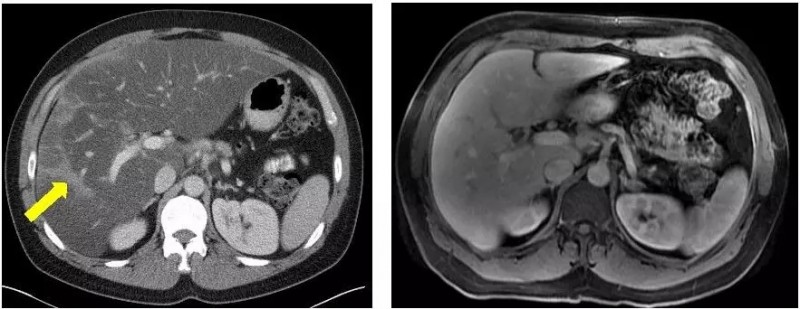

Allison,4岁因头痛恶心,发现罹患脑部和脊柱有多发的肿瘤,手术后病理检测显示她罹患非常罕见难治的肿瘤-间变性星形细胞瘤。Allison术后开始化疗,四个月后开始出现耐药,肿瘤复发。她的父母几乎咨询了全球所有顶尖的医院,得到的回复都是没有好的方案。

就在Allison的父母绝望的时候,Allison基因检测结果显示具有BRAF突变,而某些黑色素瘤也具有BRAF突变。主治医生Kieran博士建议让Allison参加dabrafenib的临床试验(dabrafenib这种药可以靶向黑色素瘤中的BRAF突变),于是,Allison便成了全球首例参加dabrafenib的临床试验的儿童脑瘤患者。治疗两个月后,奇迹出现了,头颅MRI结果显示Allison的肿瘤全部消失了。